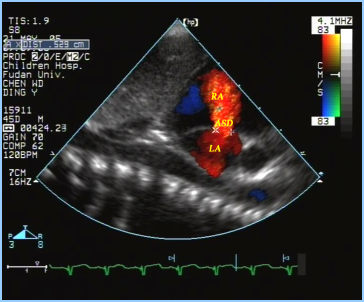

房间隔缺损:超声心动图表现

房间隔缺损(继发孔型)